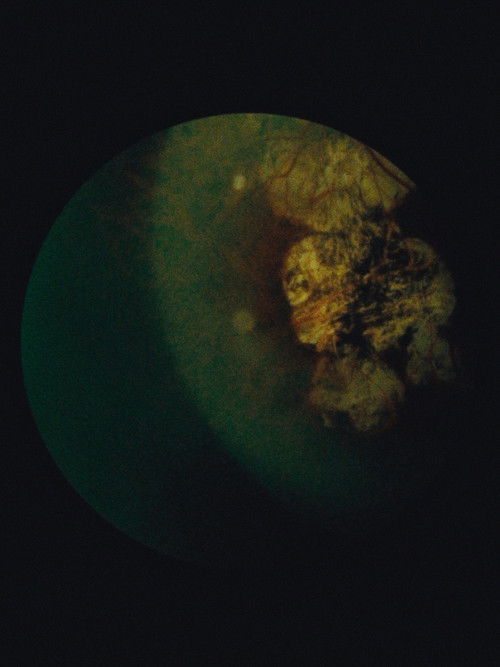

If the eyes are the window to the soul, "Immaculate Generations no. 1" presents its viewer with a singular look into thousands of souls. Equal parts Carl Sagan and William Blake, this flicker film is composed of tens of thousands of individual retinal photographs from public scientific databases. Its flickering landscapes evoke the violence of the big bang and balance somewhere between threat and seduction, like the paintings of J.M.W. Turner. Animated between 12 and 24 frames per second, they make for a dazzling rush into the maelstrom of life as we perceive it.